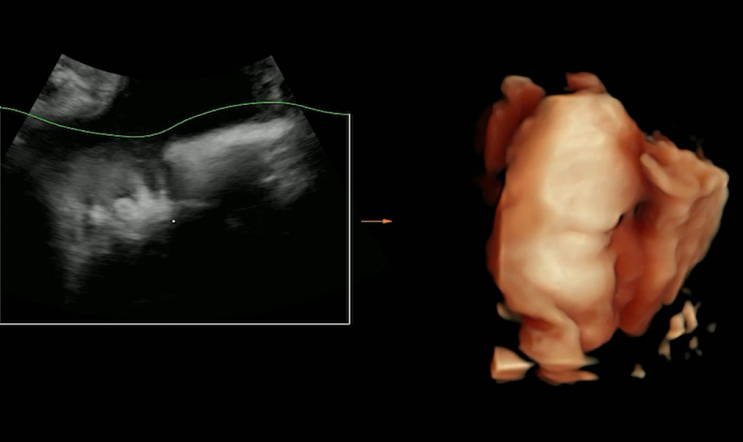

임신중일기_9. 37주차 초음파. 절대 얼굴 쉽게 보여주지 않는 한방이 ??

출산후에 적는, 출산하고도 꽤 지나서 적는 37주차 초음파 기록! 너무 오랜만에 블로그 포스팅하려니, ㅎㅎ...